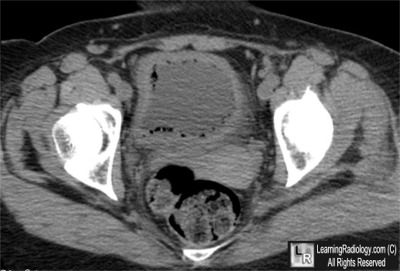

Axial CT scan through pelvis

3. Emphysematous Cystitis

Emphysematous Cystitis

- Acute inflammation of bladder mucosa and underlying muscle

- Diabetes mellitus, frequently poorly controlled, is present in 50-80% of cases

- Other predisposing conditions

- Chronic urinary tract infections

- Neurogenic bladder

- Bladder outlet obstruction

- Women are affected twice as often as men

- Gas-forming organisms most often found include E. coli and Enterobacter aerogens, with Clostridia and Candida species found on occasion